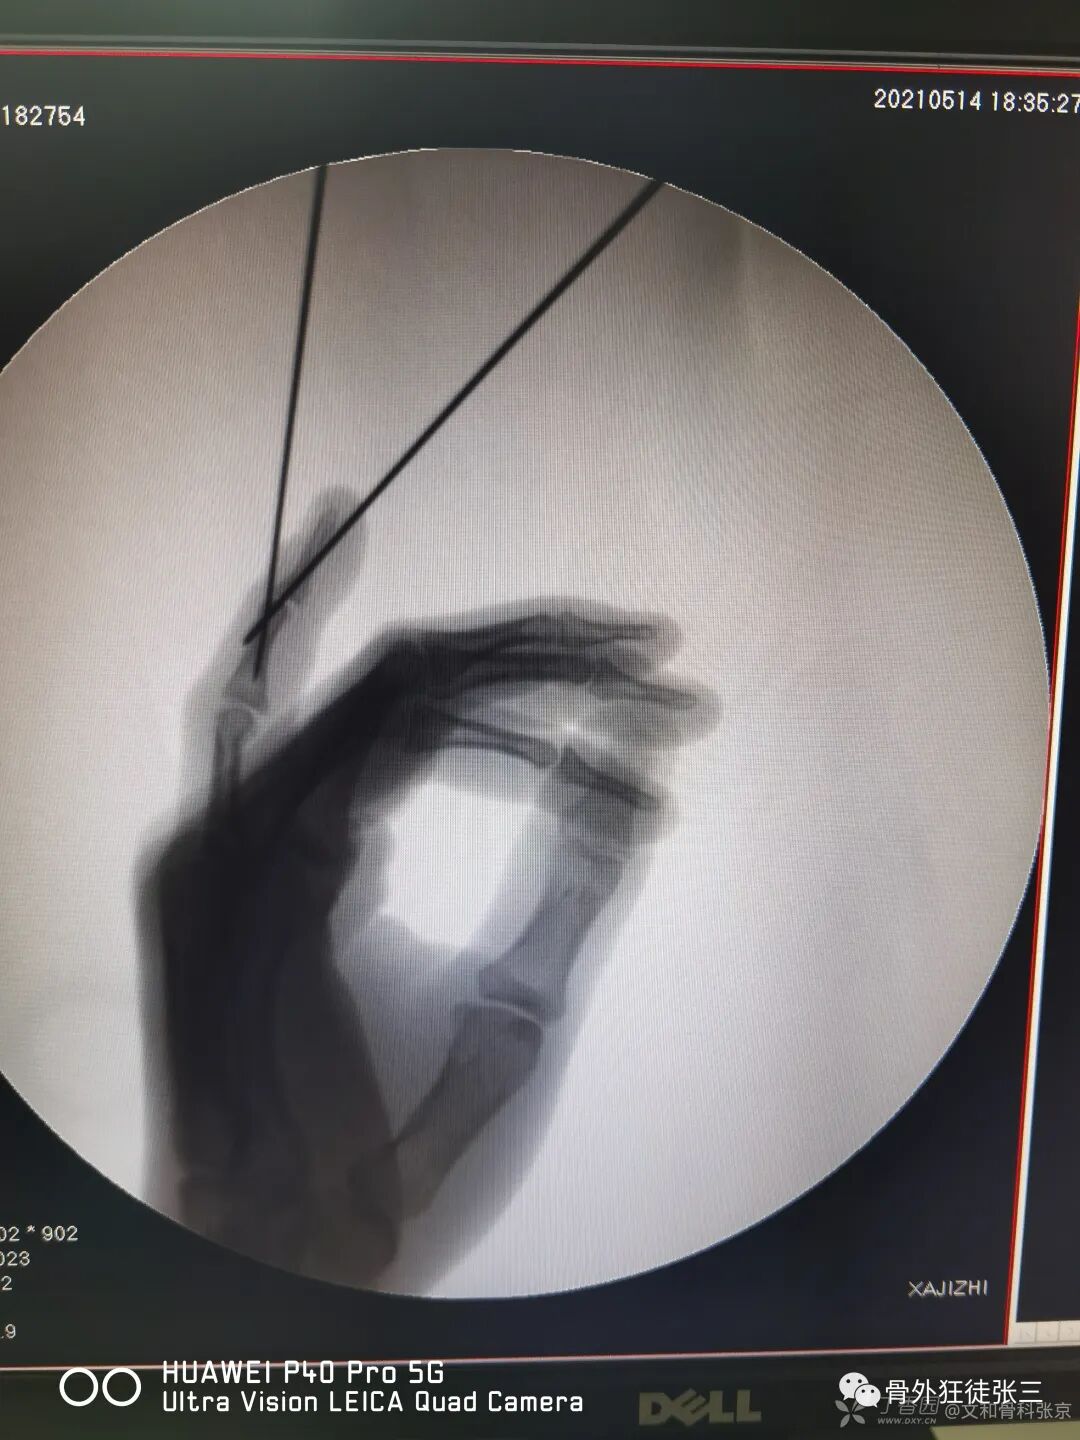

病例14,儿童髁上骨折零切开,桡侧三枚针发散固定